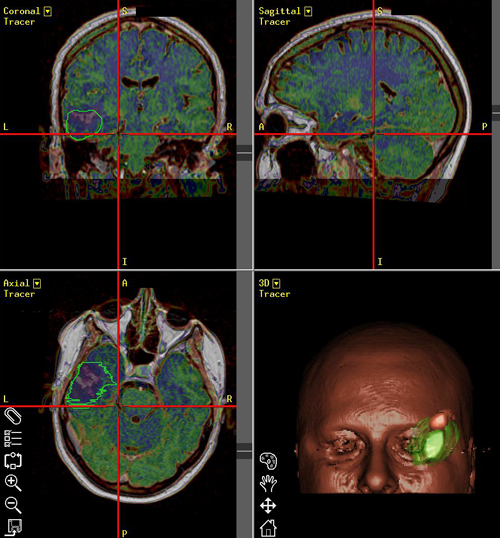

Νευροπλοήγηση σε ασθενή με κροταφικό όγκο εγκεφάλου. Ο όγκος με πράσινο περίγραμμα, η άνω κροταφική έλικα που πρέπει να διατηρηθεί με ρόζ περίγραμμα. |

Στο μοντέλο αυτό μπορούν να συνεισαχθούν και πληροφορίες από άλλες ακολουθίες της μαγνητικής τομογραφίας, π.χ. λειτουργικές ακολουθίες όπου απεικονίζονται θέσεις κέντρων του λόγου ή της κίνησης ή ακολουθίες δεσμιδογραφίας όπου απεικονίζονται νευρικές οδοί στο βάθος του εγκεφάλου. Ο χειρουργός έχει έτσι την δυνατότητα να σχεδιάσει προεγχειρητικά την επέμβαση, αποφεύγοντας για παράδειγμα προσπελάσεις που αυξάνουν τον κίνδυνο τραυματισμού ευγενών περιοχών του εγκεφάλου ή μεγάλων αγγείων. Η ταύτιση του ψηφιακού μοντέλου με τον προεγχειρητικό σχεδιασμό και της πραγματικής ανατομίας γίνεται στο χειρουργείο με την |